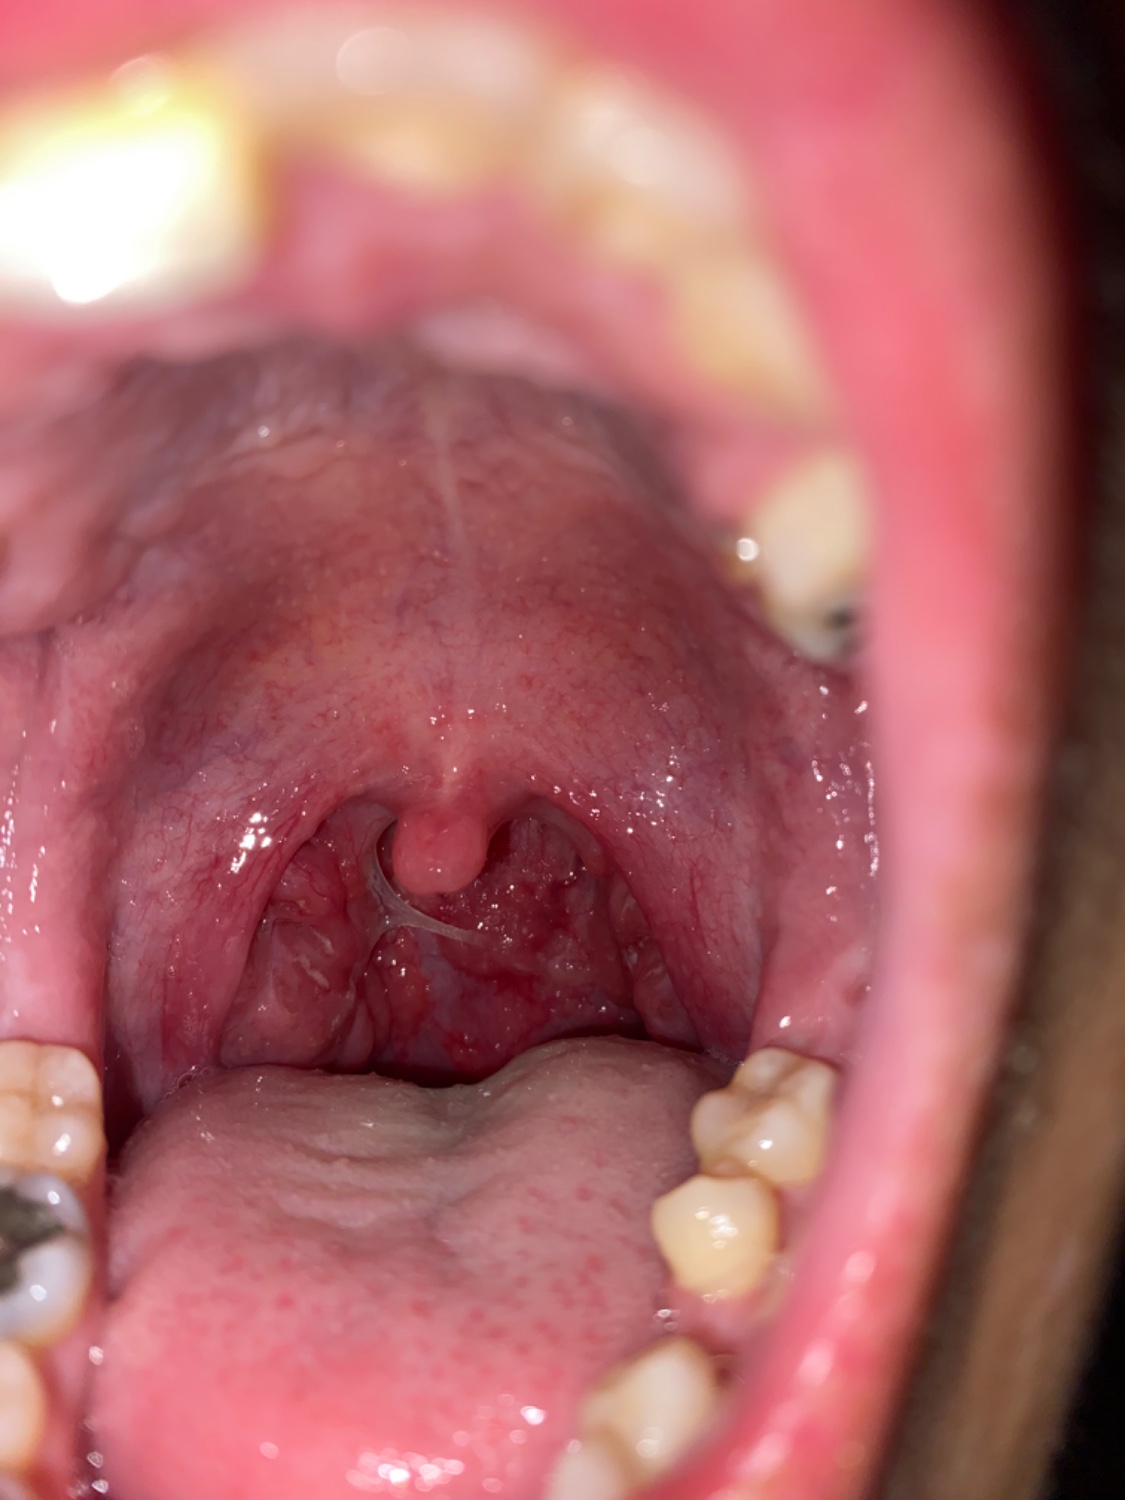

อันนี้เป็นทอนซิลอักเสบมั้ยครับ

รู้สึกว่าคันคอข้างซ้าย พออ้าปากส่องกระจกก็เป็นแบบนี้ครับ

นี่คือรูปถ่ายต่อมทอนซิลของผมเองครับ ผมป่วยเป็นหวัด แต่พอหวัดหายแล้วก็ยังไออีกหลายครั้ง เพราะรู้สึกคันคอข้างซ้าย เหมือนมีอะไรติดหรือระคายคอ แต่พอไอมากๆเข้าก็เริ่มสงสัย ผมเลยลองส่องกระจกแล้วอ้าปากดู ก็เ